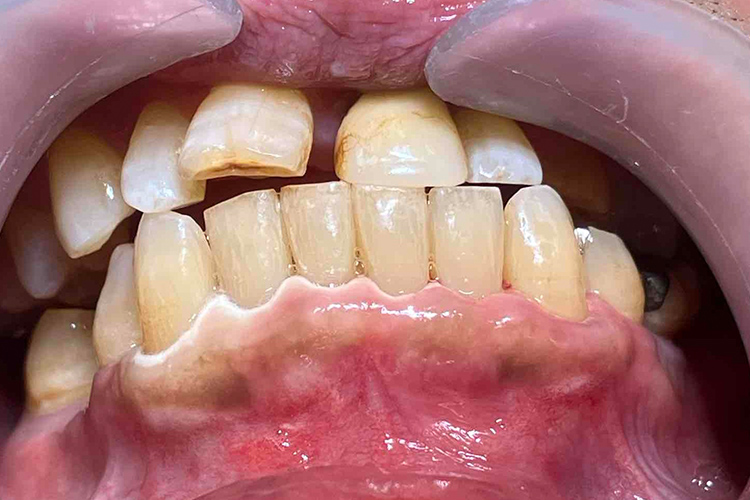

この患者様は、口腔内全体において重度の歯周病が生じており、歯磨き指導、クリーニング、Flap手術等を行ったが、歯周ポケットが深すぎるためブルーラジカル適用症例と診断し、施術を行いました。

施術前のレントゲンと口腔内写真です。施術前にプラークの除去を行ってから、施術します。

この患者様は、スケーリングより歯周ポケットが6mm以上ある患者様で患者様ご本人も歯周病になりかけている自覚がありました。

また、口臭も気になされていましたので、ブルーラジカルの適用症例と判断し、施術を行いました。

施術前のレントゲンと口腔内写真です。